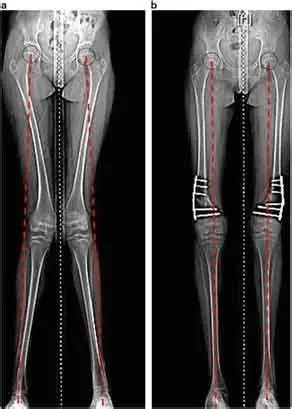

Bow legs, also known as genu varum, is a condition where the legs appear bowed outwards when standing. This condition can cause discomfort, pain, and even difficulty walking. In severe cases, surgery may be required to correct the alignment of the legs. In this article, we will discuss the causes, symptoms, and treatment options for bow legs, including the various surgical procedures available.

The treatment options for bow legs will depend on the severity of the condition and the underlying cause. Some common treatments include

Knock Knees, also known as genu varum, is a condition where the legs appear bowed outwards when standing. This condition can cause discomfort, pain, and even difficulty walking. In severe cases, surgery may be required to correct the alignment of the legs. In this article, we will discuss the causes, symptoms, and treatment options for Knock Knees, including the various surgical procedures available.

The treatment options for knock knees will depend on the severity of the condition and the underlying cause. Some common treatments include